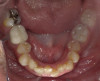

Fig 5. Clear aligner treatment was recommended to this patient, who presented with a missing lower molar combined with

posterior and anterior malocclusion.

Figure 5

Fig 6. Clear aligner treatment was recommended to this patient, who presented with a missing lower molar combined with

Figure 6

Fig 7. Clear aligner treatment was recommended to this patient, who presented with a missing lower molar combined with